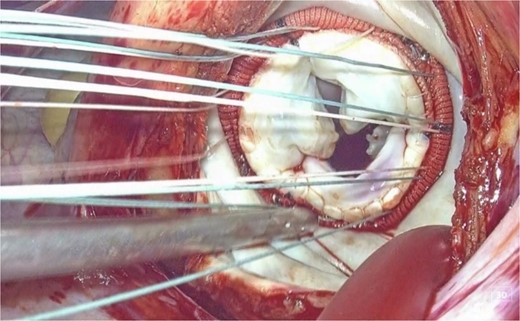

This is believed to be the first report of a totally 3D endoscopic mitral valve replacement in SIT. We have demonstrated that totally endoscopic surgery is feasible in cases of SIT and that its advantages can be offered to the patient. Several precautions were necessary for the success of this procedure given the anatomy of SIT. The first was the placement of the surgical instruments under the preoperative mirror image. All settings, positions, and instruments must be placed in opposite directions, and the cannulation sites must be completely opposite. The second is to adapt to the inverted left–right anatomy of the thoracic cavity. It is important to note that the main incision in the fourth ICS is on the left side of the mitral valve, contrary to the usual approach. This means that needles and sutures, prosthetic valves, and other devices are inserted through the main incision on the left side toward the mitral valve using a left-handed forceps; if we are right-handed, we must switch the needle threads to a right-handed needle holder in the thoracic cavity for each suture (Figs 3 and 4).

3D endoscopic view of the intraoperative field: We are right-handed, needle thread inserted by using the left-handed forceps is switched to the right-handed needle holder to perform the suture (a → b → c → d).